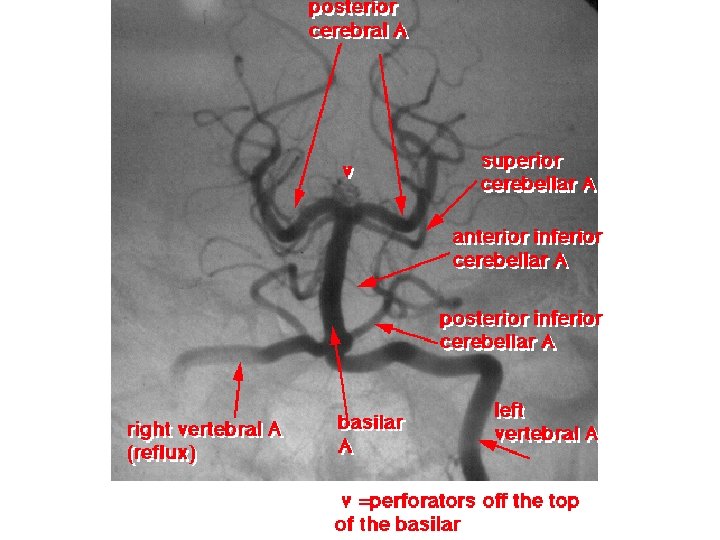

Arteria basilaris 2 aa. vertebrales → a. basilaris • a. inferior anterior cerebelli – a. labyrinthi • aa. pontis • aa. mesencephalicae • a. superior cerebelli → aa. cerebri posteriores circulus arteriosus cerebri Willisi

Arteria vertebralis • pars prevertebralis • pars cervicalis s. transversaria – forr. transversaria C 6 -C 1 – rr. spinales et musculares • pars atlantica – sulcus a. v. (canalis a. v. ) – membrana atlantooccipitalis post. – foramen magnum • pars intracranialis – rr. meningei – a. inferior posterior cerebelli • a. spinalis post. – a. spinalis ant. • unpaired from paired short innominate source arteries